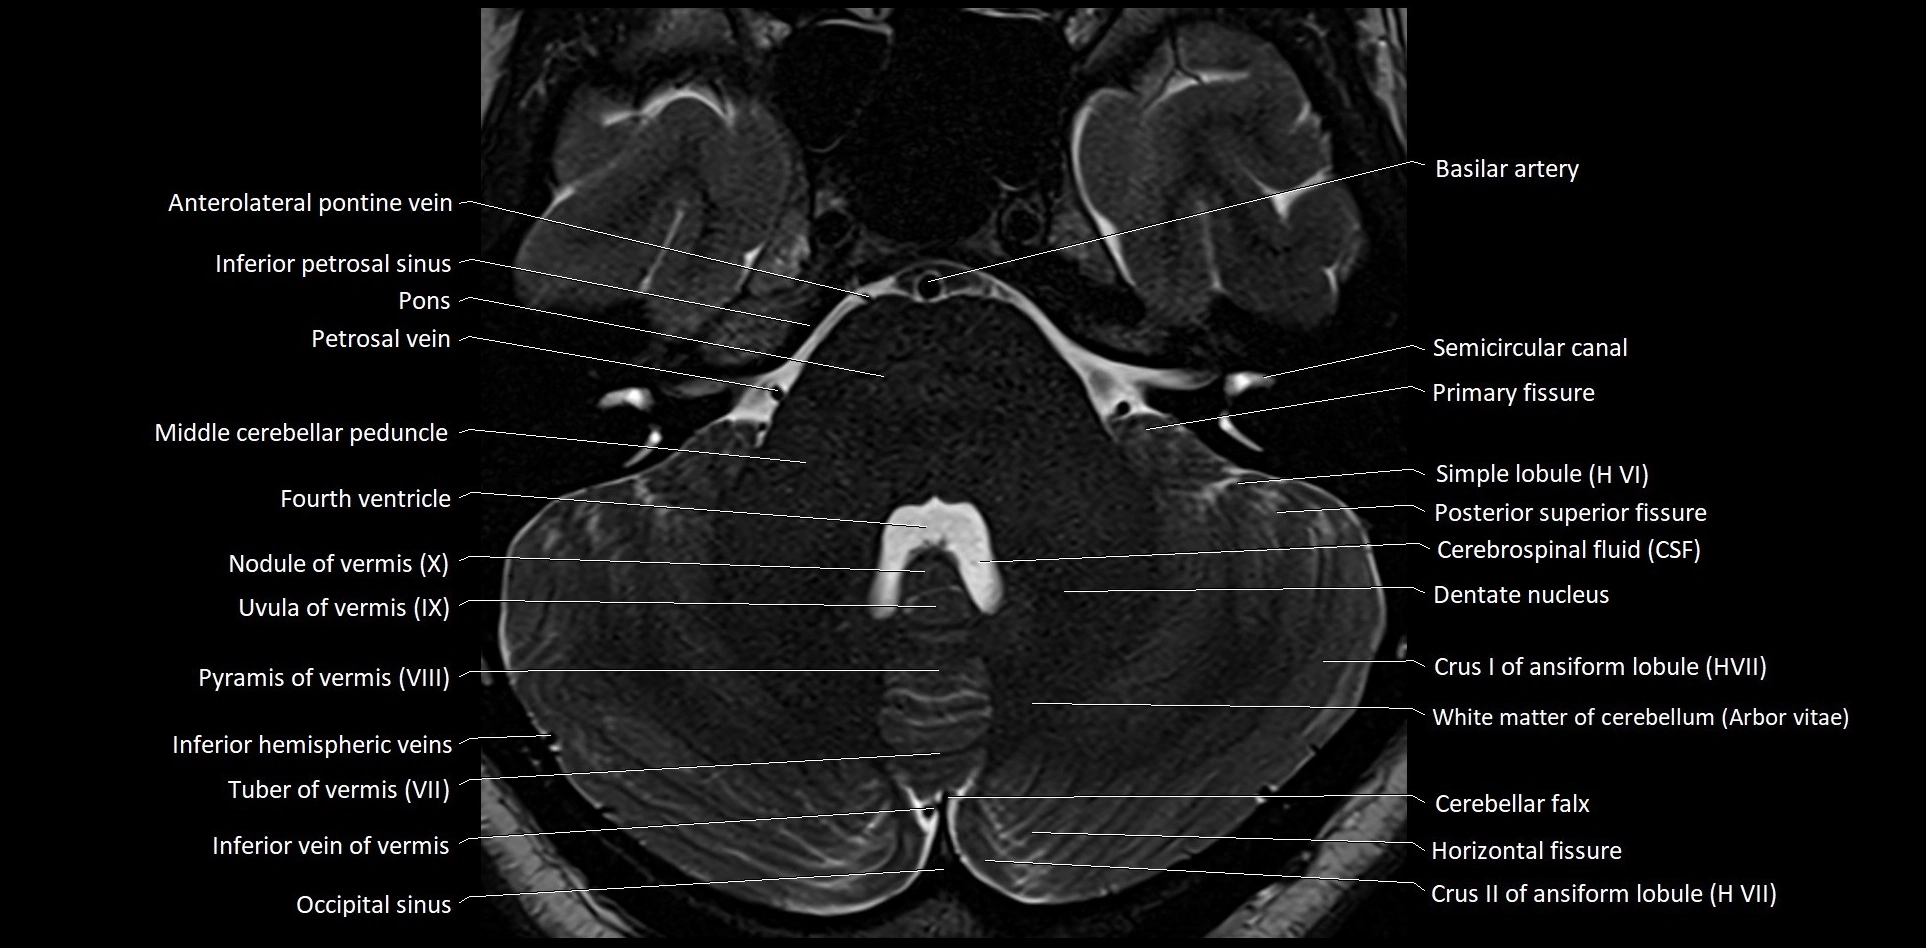

MRI images